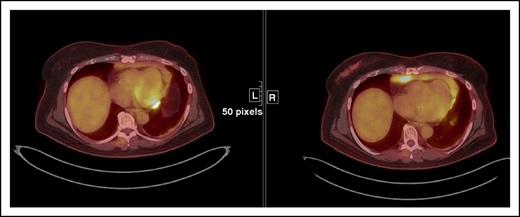

3. Increase in FDG uptake of 1 or more lesion(s) without a concomitant increase in lesion size or number [IR(3)] (Figure 5)

Increased immune activity at the site of tumor may manifest as an increase in FDG uptake. Therefore, by itself, changes in uptake should not trigger an assignment of PD with checkpoint inhibitors. The magnitude of increase in uptake in an immune-mediated flare compared with that in true tumor progression is not yet known. It is important to investigate this finding, especially in conjunction with biopsies of the lesion in question.

IR(3) showing an increase in FDG uptake in a paracardiac node suggestive of lymphoma without a concomitant increase in size of lesion(s) that meets PD criteria.

While awaiting a better characterization of this phenomenon, we propose that, under the modified response criteria, an increase in FDG avidity of 1 or more lesions suggestive of lymphoma, without a concomitant increase in size of those lesions meeting PD criteria does not constitute PD.